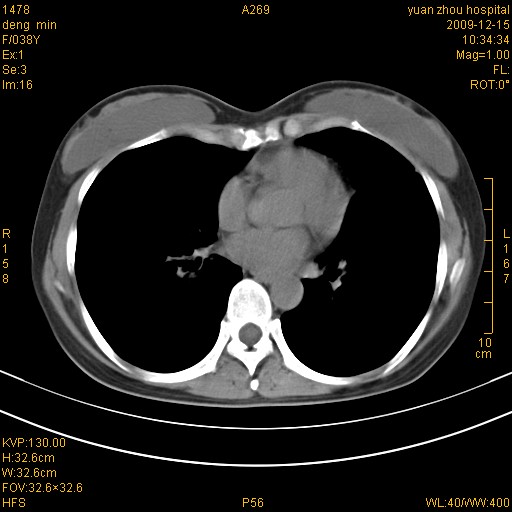

标题: CT23919:F38Y 咳嗽月余 [打印本页]

标题: CT23919:F38Y 咳嗽月余

右肺中下叶、左肺上叶舌段及左肺下叶支气管扩张合并感染。